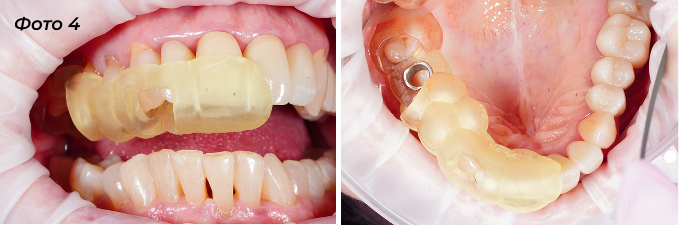

Фото 4 — шаблон непосредственно в полости рта, закреплен на зубах.